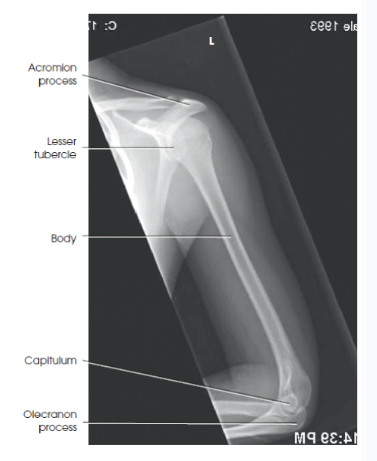

What are the proximal anatomical structures of the humerus?

The head, anatomic neck, surgical neck, greater tubercle, and lesser tubercle.

Name the distal anatomical structures of the humerus.

The medial epicondyle, lateral epicondyle, trochlea, capitulum, coronoid fossa, and olecranon fossa.

What are the evaluation criteria/structures shown for an AP humerus?

Elbow and shoulder joints must be in the image

Humeral epicondyles without rotation

Humeral head and greater tubercle in profile

outline of the lesser tubercle, located between the humeral head and the greater tubercle

bony trabecular detail and surrounding soft tissues